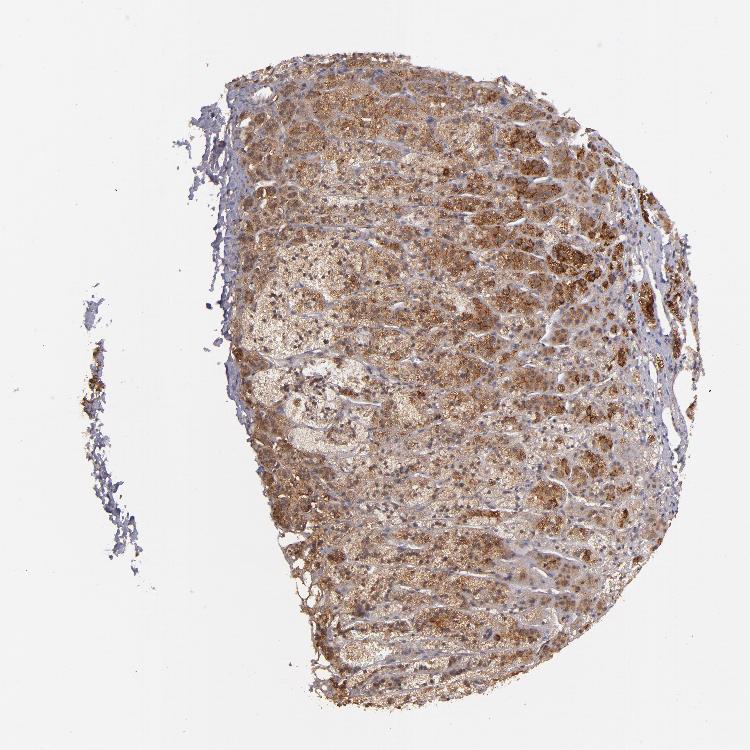

ADRENAL GLAND - Antibody stainingi

Antibody staining in the annotated cell types in the current human tissue is reported as not detected, low, medium, or high, based on conventional immunohistochemistry profiling in selected tissues. This score is based on the combination of the staining intensity and fraction of stained cells.

Each image is clickable and will lead to virtual microscopy that enables deeper exploration of all samples and also displays staining intensity scores, fraction scores and subcellular localization as well as patient and tissue information for each sample.

Antibody HPA002898

Glandular cells Medium